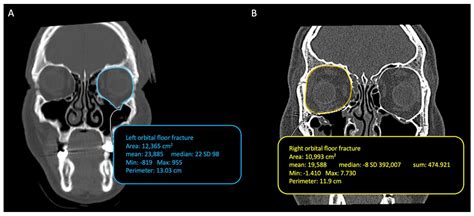

To accurately diagnose an orbital floor fracture, healthcare providers rely on a combination of physical examination and advanced imaging. During the physical exam, a surgeon will test the range of motion of your eyes and check for nerve sensation in the face. To confirm the diagnosis, the gold standard is a Computed Tomography (CT) scan of the orbits.

CT Scan (Coronal View) Best visualization of the orbital floor and sinus involvement.

• The fracture is large, leading to a high risk of long-term deformity.